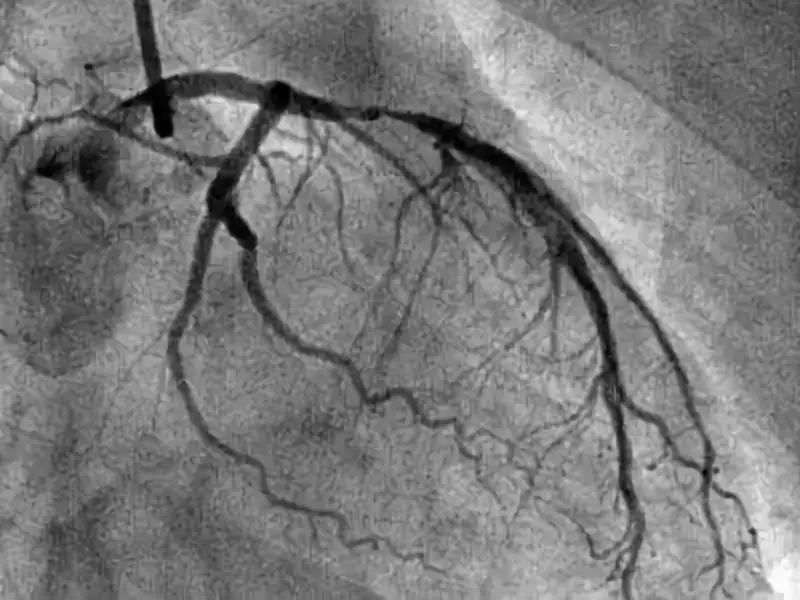

在心内科,如果医生高度怀疑患者的冠脉存在堵塞,或者怀疑患者的心脏异常,就会让患者去做一个冠脉造影。

这种高科技可以让医生更清晰地看到你心血管、以及心脏的目前情况,以便医生做出正确的诊断。

冠脉造影检查,是一种针对冠心病检查的重要方法,它的有效率非常高,能准确且清晰的显示患者冠状动脉的解剖结构以及它可能存在的畸形、阻塞性位置,是目前唯一也是最先进的心血管检查方式。

冠脉造影,有一项是看患者的冠脉血流分级:

0级,无灌注,患者冠脉闭塞部位及远端无造影剂充盈。

1级,造影剂通过闭塞部位,但是远端血管无造影剂。

2级,造影剂能抵达远端血管,但是速度缓慢。

3级,造影剂快速抵达远端血管。

通过分级,可以一定程度判断狭窄程度。另外,医生建议如果你要去做冠脉造影,前一天一定要做好准备,首先要休息好,以免在做冠脉造影时出现意外。